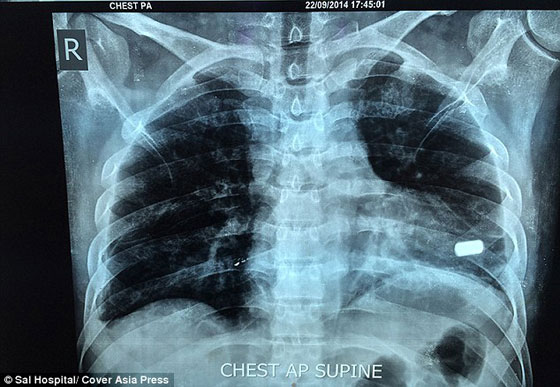

غير أن شارما اضطر الثلاثاء إلى السفر إلى أحمد أباد غربي الهند للخضوع لعملية جراحية لإزالة الرصاصة من قلبه في مستشفى سال الخاص. وكانت العملية معقدة للغاية جراء استقرار الرصاصة في الجزء الأسفل من القلب، بالقرب من البطين الأيسر، بحسب ما نقلت صحيفة الغارديان البريطانية.

وأكد الجراح في مستشفى سال، أنيل جاين، أن العملية الجراحية استغرقت زهاء 3 ساعات لإزالة الرصاصة، موضحاً أنها "استقرت بشكل أفقي بين الصمامين". وأضاف: "ولأن المريض فقد الكثير من الدم بعد الحادث، كان لزاماً علينا أن نكون حذرين للغاية، أما كيف عاش المريض لهذه الفترة ووصل إلينا فكله محض قدر". وقال الجراح إن شارما سيتمكن من العودة إلى العمل في غضون شهر، وهو يرقد حالياً في وحدة الرعاية المكثفة في المستشفى.